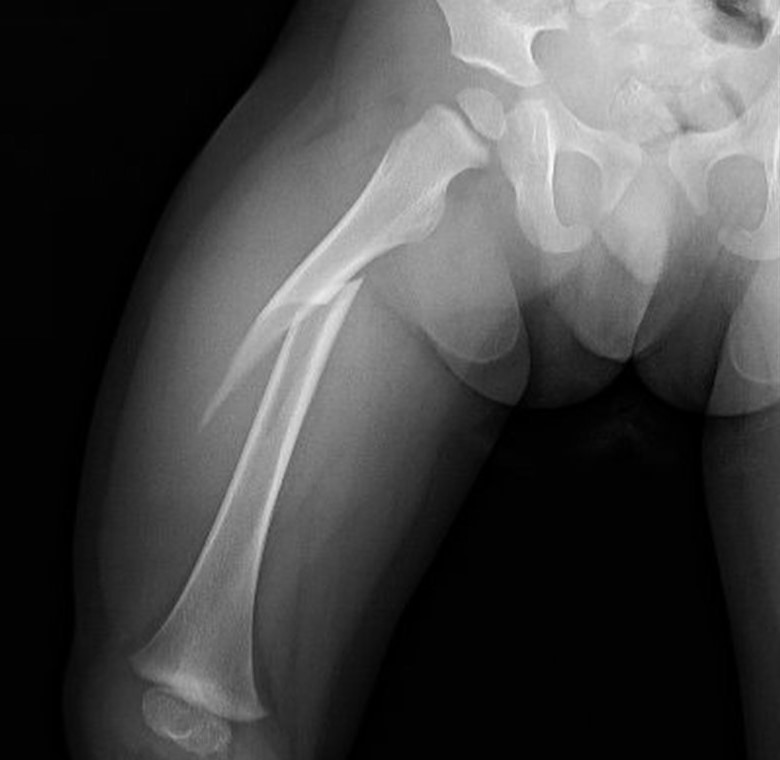

Fractura de fémur